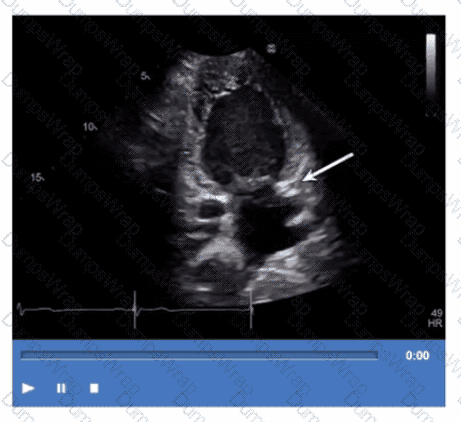

Which step is next in further evaluation of the abnormality shown in this video?

Options:

Administration of agitated saline with cough

Administration of agitated saline from right antecubital vein

Administration of agitated saline with Valsalva maneuver

Administration of agitated saline from left antecubital vein

Answer:

CExplanation:

Comprehensive and Detailed Explanation From Exact Extract:

The video suggests an atrial septal abnormality possibly a patent foramen ovale or interatrial shunt. To evaluate for right-to-left shunting across an atrial septal defect, the administration of agitated saline contrast with a Valsalva maneuver is the next best step.

Valsalva increases right atrial pressure transiently, promoting transient right-to-left shunting, making microbubbles visible in the left atrium if a shunt is present. Administration without Valsalva reduces sensitivity. The choice of arm vein (right or left) is less critical.

This diagnostic technique is well described in ASE adult congenital heart disease guidelines and echocardiography contrast protocols【12:ASE Contrast Echocardiography Guidelines†p.190-195】【16:Textbook of Clinical Echocardiography, 6e†p.575-580】.